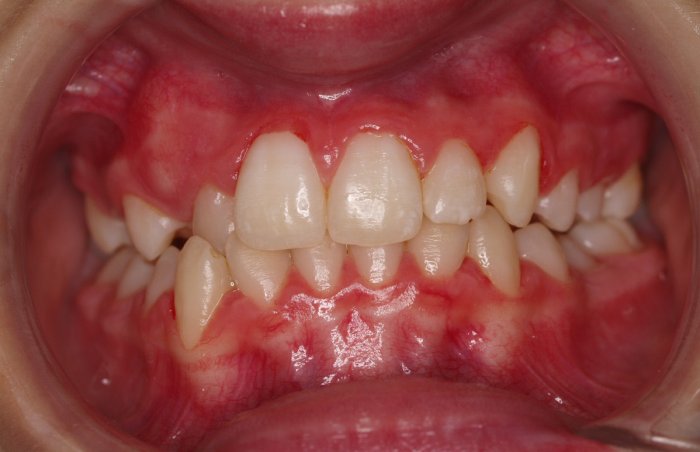

El paciente A.J. de 11 años, acude a nuestra consulta con apiñamiento maxilar importante. El canino lateral (12) está en mordida cruzada. Presenta una Clase II molar y canina, y la línea media está desviada. Se realizó un tratamiento con brackets autoligables metálicos de smartclip 022. La duración del tratamiento fue de 22 meses.